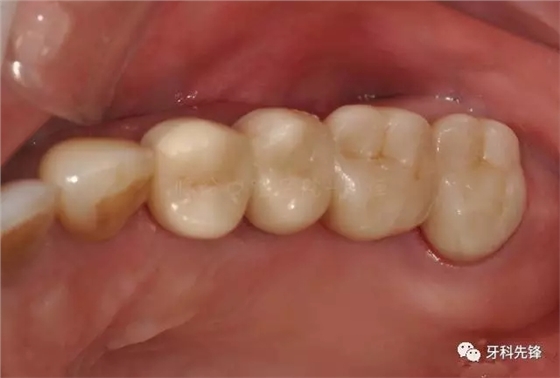

圖29術(shù)后頰面照

640.webp (33).jpg